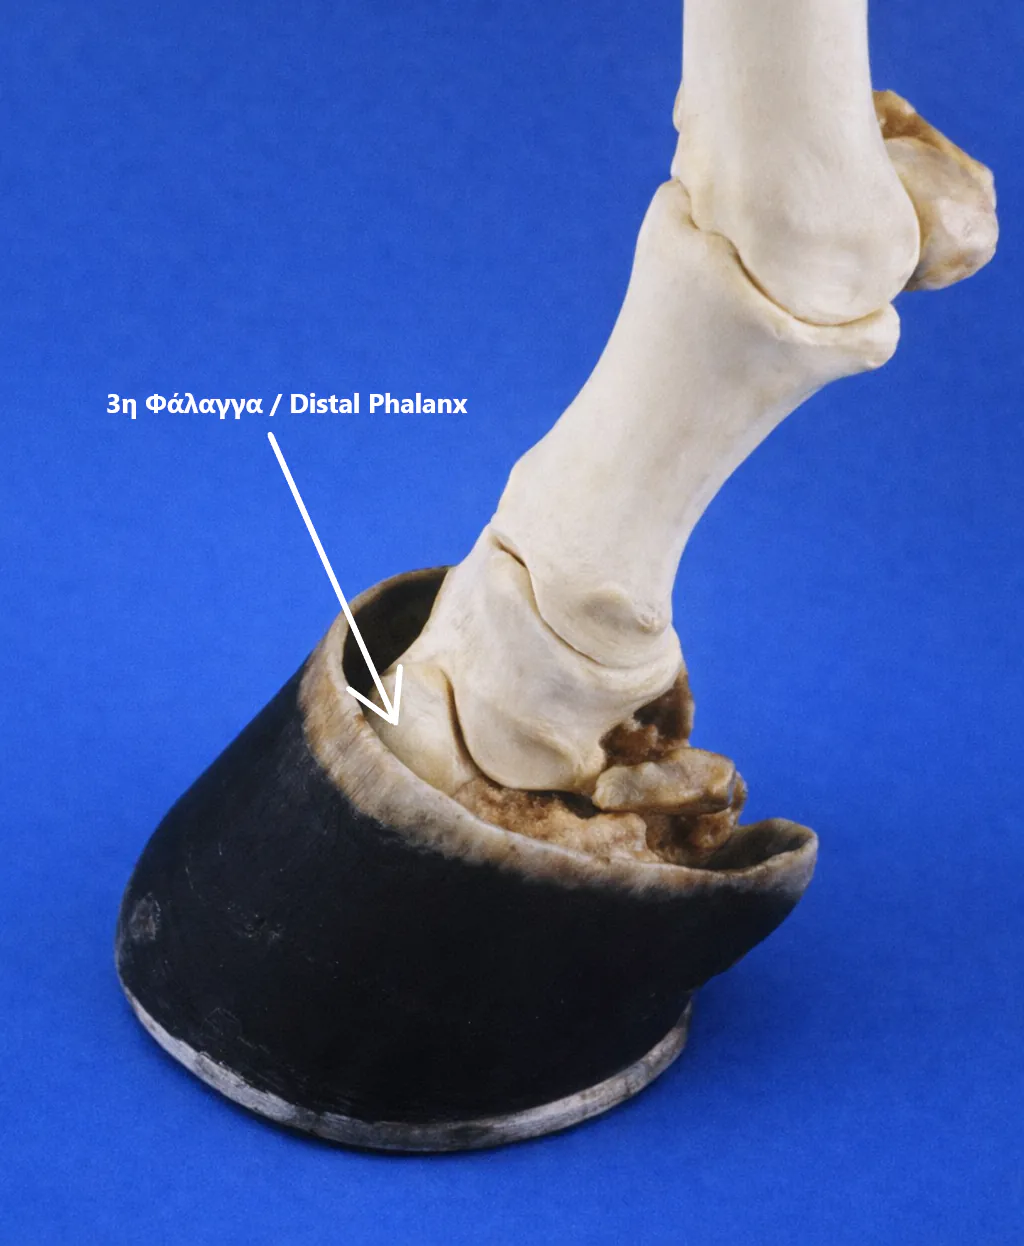

Laminitis occurs when the distal phalanx (coffin or pedal bone, P3) fails to remain securely attached to the lamellae lining the inner surface of the hoof capsule.

In the healthy horse, this attachment forms a highly specialised suspensory apparatus. The inner hoof wall is folded into microscopic, leaf-like structures (lamellae) that increase surface area and allow strong yet flexible load distribution.

When lamellar failure occurs, the weight of the horse and the forces of locomotion drive the distal phalanx downward or cause it to rotate within the hoof capsule. In severe cases, this displacement may result in penetration of the sole by the distal phalanx. The associated vascular compromise, tissue damage and inflammation lead to severe, unrelenting pain and characteristic lameness.